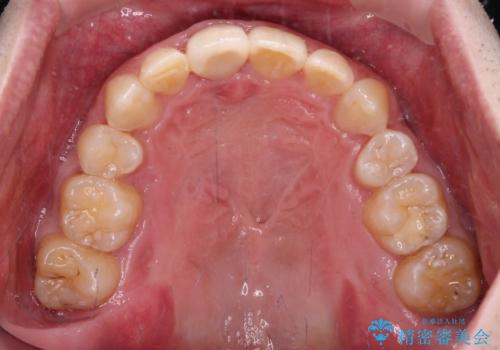

通常では速やかにオールセラミッククラウンにて補綴治療を行うのですが、デコボコしている歯列も気になっていたため、事前に矯正治療を行うこととしました。

上顎歯列の叢生が著しかったため、上顎左右第一小臼歯2本を抜歯し、目立たないワイヤー装置にて治療を進めることとしました。

矯正治療後にはオーダーメイドタイプのオールセラミッククラウンを装着し、自然な口元に仕上がりました。